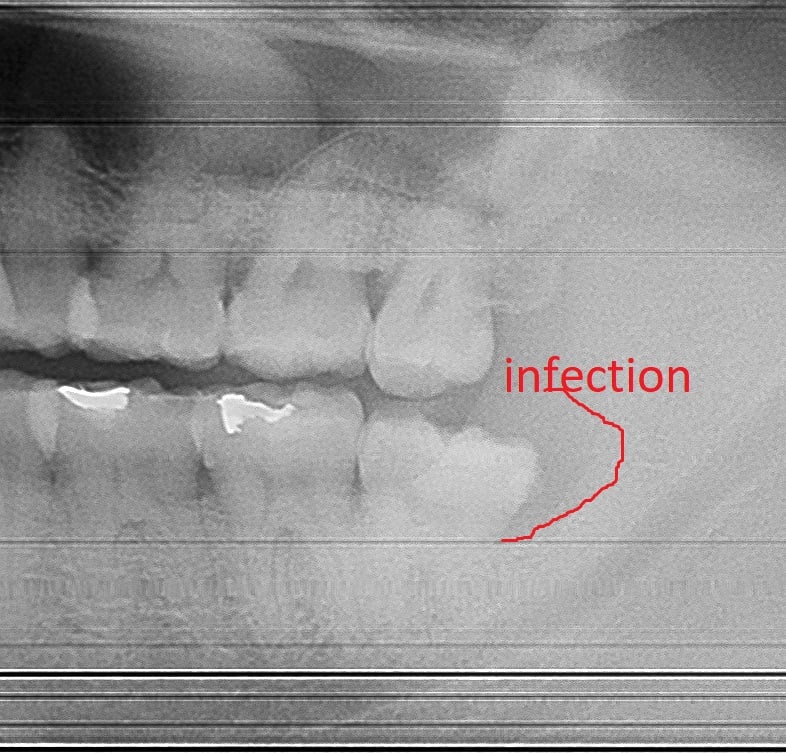

A common dental emergency frequently seen in dental offices is pain caused by a wisdom tooth. Very often gum infection around the wisdom tooth, called pericoronitis is the source for discomfort. Usually, this infection requires the removal of the offending wisdom tooth for the pain to be resolved.

Wisdom tooth infection, also called Pericoronitis, is the most common cause for wisdom tooth extractions. It’s very difficult to keep wisdom teeth clean because they’re often covered by gum tissue. Over time, the food particles that are not cleaned under the gum will become a source for bacterial growth. This infection will cause swelling and discomfort for the patient. The most effective treatment is wisdom tooth extraction.

Antibiotics often take several days (2-3 days) to be effective. Patients with wisdom tooth pain will usually benefit the most with wisdom tooth extraction combined with a course of antibiotics. When patients just take antibiotics without the removal of the infected wisdom tooth, the infection will usually return within a few months.